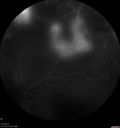

PDR and Vitreous Hemorrhage - High Risk Left Eye - Low Risk Right Eye

50 year old man with type I diabetes mellitus for 26 years. New Vitreous Hemorrhage in the left eye. Both eyes have NVE. Both also have foveal hypoplasia